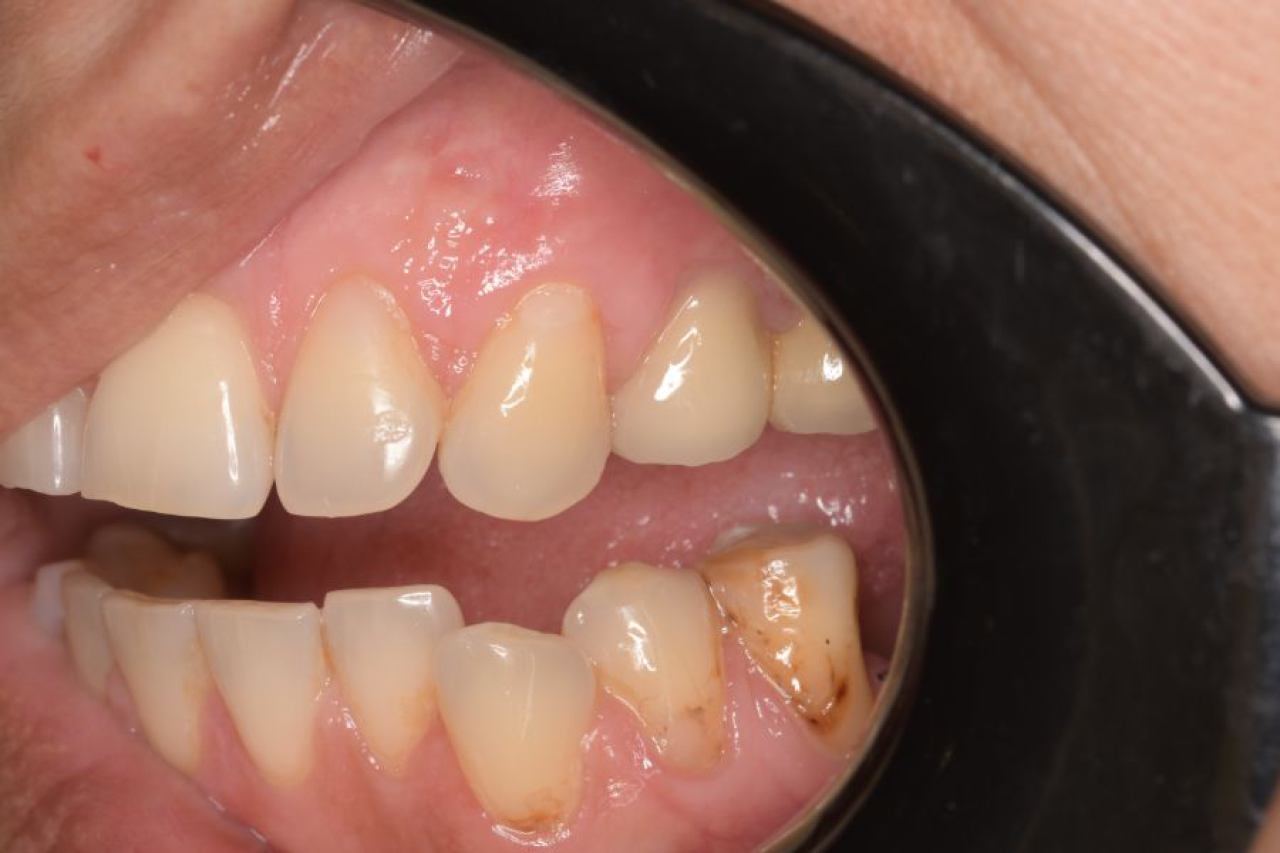

Parodontologija i kirurgija

Parodontologija je grana dentalne medicine koja se bavi zdravljem potpornih struktura zuba (parodonta). Parodont se sastoji od zubnog mesa (gingiva), kosti i vlakana koja vežu zub za kost (parodontalni ligament).

Ovo je grana kojoj Marković Dental Clinic pridaje puno pažnje jer je vrlo kompleksna i bitna za cijelo oralno zdravlje.